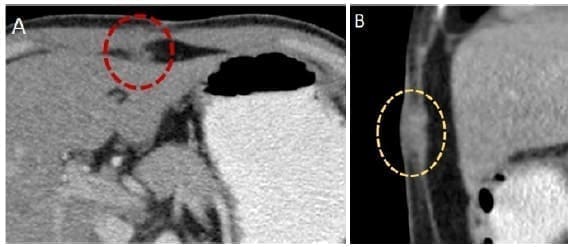

Ante la presencia de estadios T1b o más, se deben realizar estudios imagenológicos de estadificación clínica, que deben incluir imágenes de alta resolución de tórax, abdomen y pelvis, en busca de linfadenopatías regionales o metástasis a distancia (Figuras 2, 3 y 4), además se debe considerar la realización de una laparoscopia (Figura 5) 30.

Figura 4. Tomografía axial que muestra siembras tumorales en la pared abdominal y en el trayecto de los puertos, en paciente con antecedente de colecistectomía vía laparoscópica y hallazgo de CIVB. Siembra en el ligamento redondo, corte axial (A). Siembra en los músculos de pared abdominal, corte sagital (B).